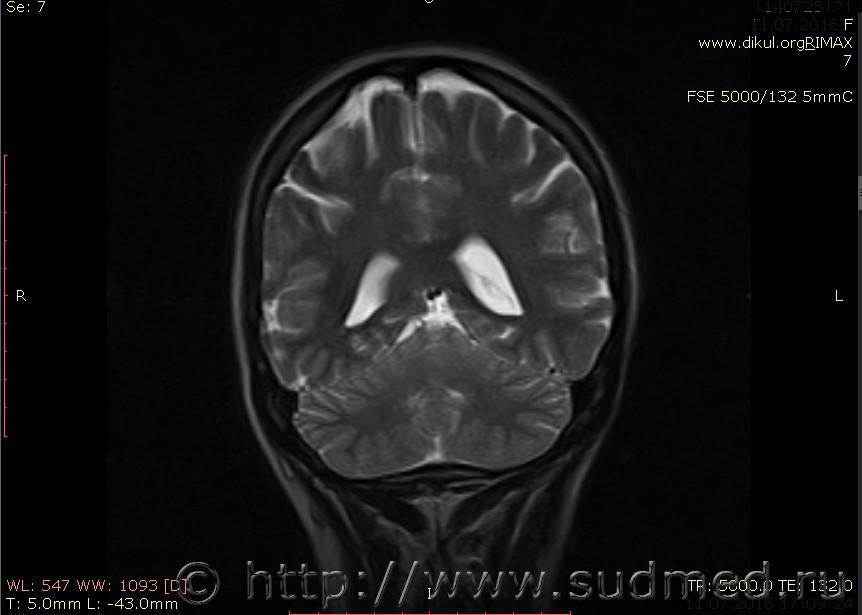

МРТ головного мозга показало: МР-данных за наличие очаговых изменений в веществе головного мозга на момент исследования не выявлено. МР-признаки нарушения соотношения в атланто-осевом суставе. Определяется ассиметрия положения зубовидного отростка С2 относительно боковых масс С1(справа 6,5; слева 4 мм.)

Сама по себе эта информация даёт основания подозревать вывих первого шейного позвонка, но однозначно не свидетельствует о наличии вывиха. Нужно смотреть на снимках наличие реакции со стороны мягких тканей, в т.ч. связочного аппарата, нужно анализировать особенности неврологической патологии, её динамику и проч.

Запрошен электронный вариант снимков из учреждения, где делалось МРТ. Т.к. с самого снимка делать копии не получается,очень мелкие кадры. Завтра попробую вставить в сообщение. (Но СМЭ снимок не смотрел, смотрел только мед.карту, в которой находилось описание МРТ).

Посмотрите пожалуйста снимки, надеюсь на них видны позвонки С1,С2?

Прошу прощения, попробую снова прикрепить файлы. Данные учреждения и пациента убраны.